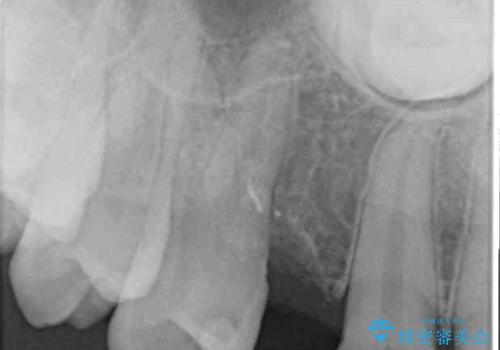

- 永久歯が生えてこず、欠損になっていることを気にして来院された患者様です。

CT撮影を行ったところ、埋もれている犬歯を牽引して萌出させることは不可能と判断し、インプラントによる補綴治療を行うこととしました。